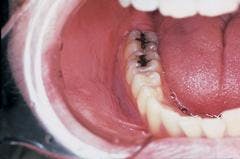

Intraoral examination revealed a large, diffuse white area in the mucobuccal fold (see photo). The lesion appeared wrinkled or corrugated in texture. The lesion could not be removed by wiping or scraping. Further oral examination of the oral soft tissues revealed no other lesions present.

Although a smokeless tobacco keratosis is typically seen in young males, this lesion may be seen in any individual who uses a smokeless tobacco product. The lesion has a fairly characteristic clinical appearance and is found at the preferred site of tobacco placement. If more than one intraoral location is used to hold the tobacco products, multiple and less prominent lesions may be seen. The most frequent sites of involvement include the mucobuccal fold area in the incisor and molar regions.

The typical smokeless tobacco keratosis appears white with a raised or flat contour. The texture of the lesion appears smooth, granular, or corrugated. The appearance of the keratosis has been compared to that of an "ebbing" tide. A smokeless tobacco keratosis is asymptomatic and is usually discovered upon routine oral examination.